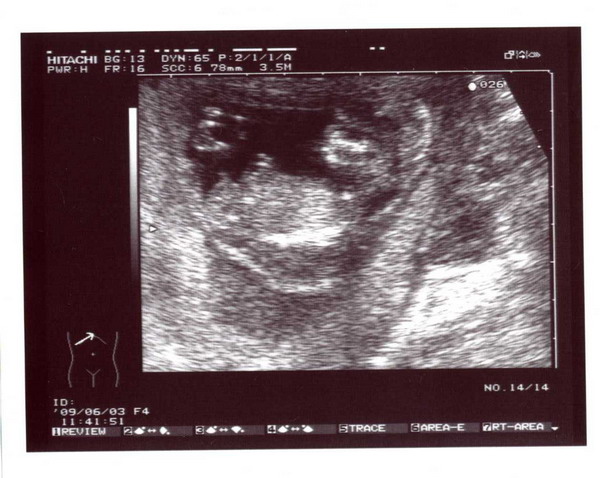

Na vajon ki lapul a pocakban????